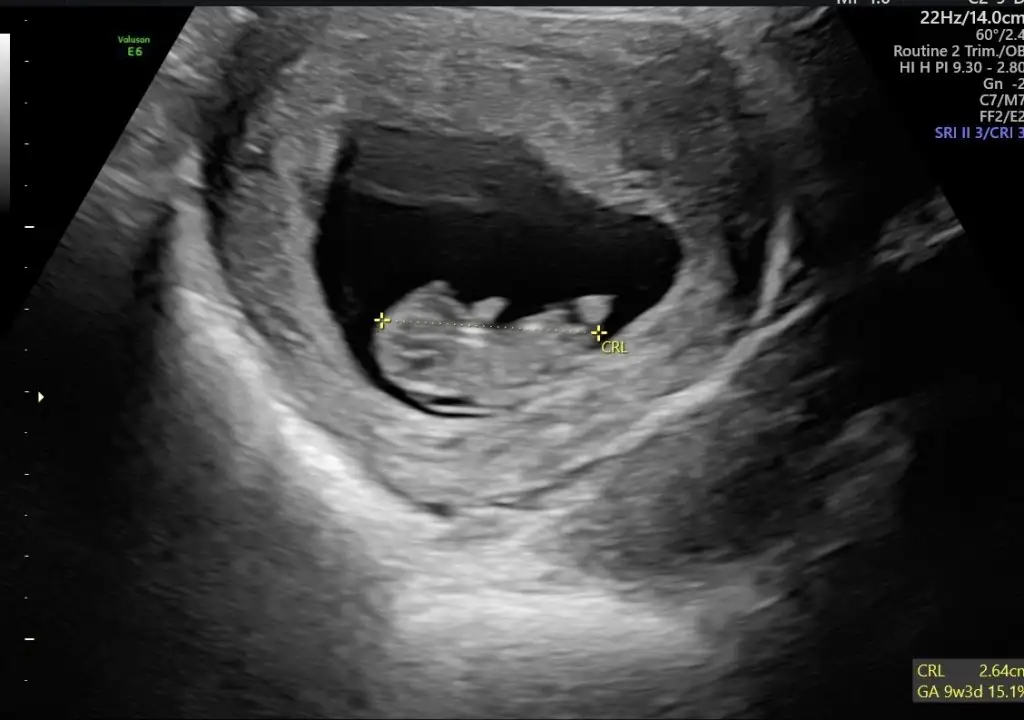

5., 6., ve 9+5 .haftaya ait karından ultrason görüntüleri :)Eki Görüntüle 3273013 Eki Görüntüle 3273014 Eki Görüntüle 3273015

Erkek bebek 6 haftalık ultrasona göre kuzum